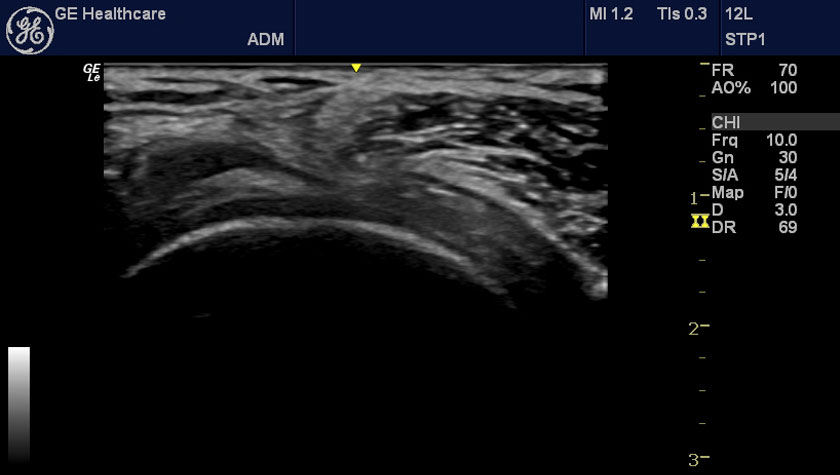

Галерея изображений:

2 - бедро, виртуальный конвекс, датчик L4-12t-RS